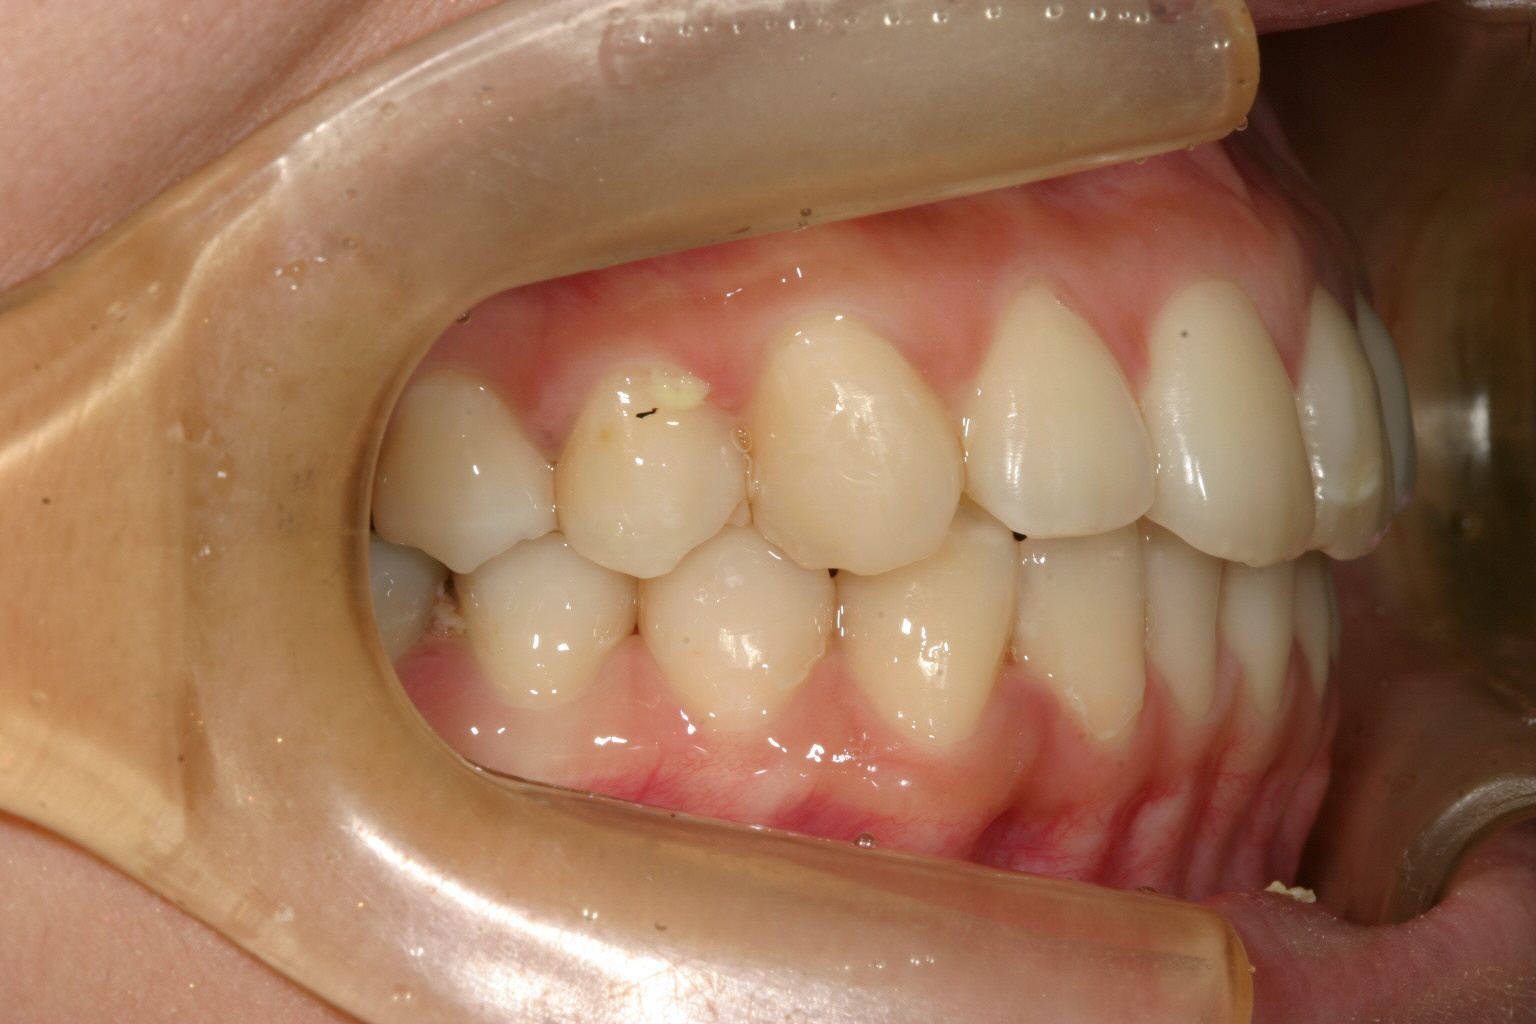

前歯も左側小臼歯も綺麗に回転戻しました。

下顎も綺麗に改善されています。

側面観も大変綺麗になりました。